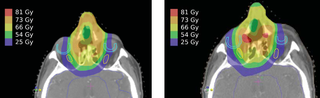

File:DBP.HNC1.png